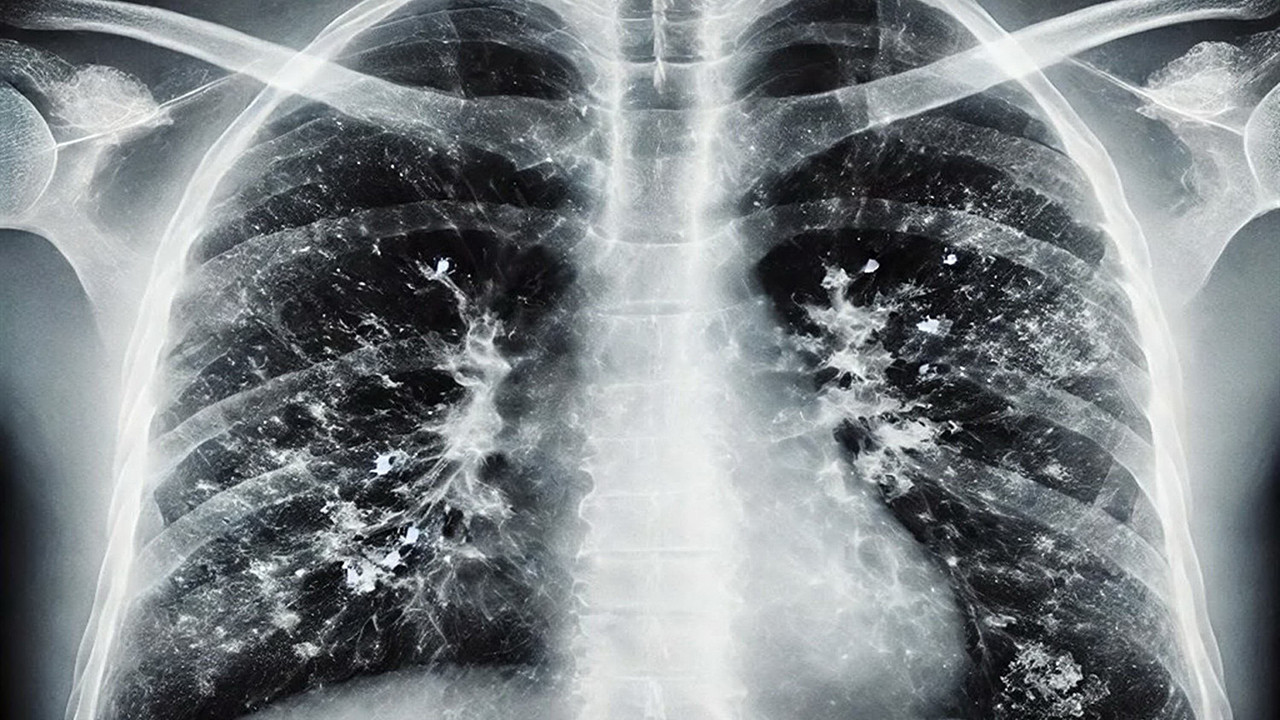

Gribal enfeksiyonlar açısından influenzada ciddi bir yükseliş olduğunu ifade eden Prof. Dr. Şener, "İnfluenza dışında RSV ve rinovirüs de görülüyor. Gribal enfeksiyon geçirdikten sonra bakteriyel enfeksiyonlar, süperenfeksiyon olarak ortaya çıkıyor. Bu süperenfeksiyonlar, bakteriyel olduğunda bazen ağır tablolara neden olabiliyor. Zatürre, pnömoni, akciğer iltihabı gibi durumlar hastaneye yatışa hatta oksijen desteği ihtiyacına sebep olabilecek klinik tablolara yol açabiliyor. Bu açıdan dikkat etmek lazım. Aile hekimine başvurduğunuzda ücretsiz grip aşınızı olabilirsiniz" dedi.